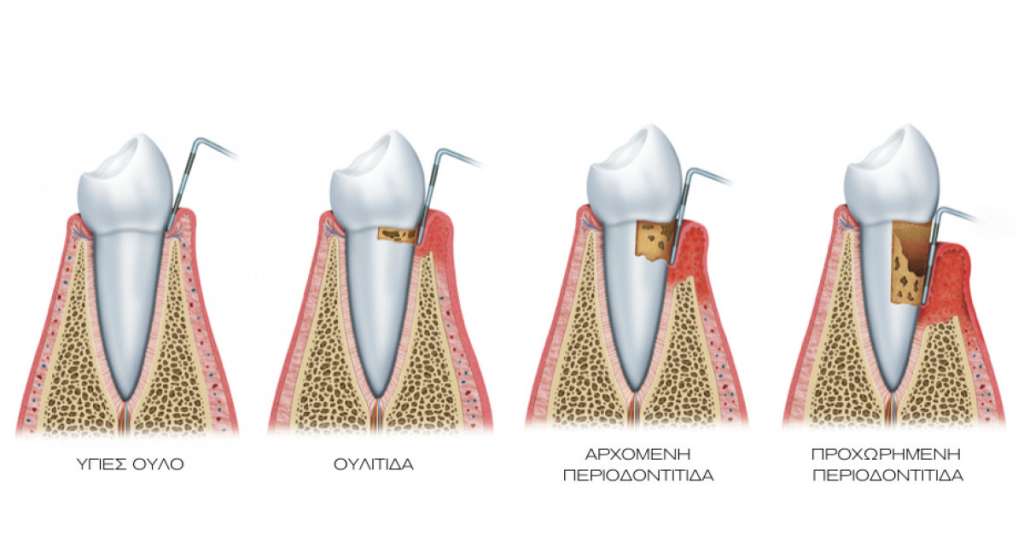

Η Περιοδοντολογία αποτελεί έναν από τους βασικότερους τομείς της σύγχρονης οδοντιατρικής, καθώς ασχολείται με τη φροντίδα και τη θεραπεία των ιστών που στηρίζουν τα δόντια: ούλα, περιοδόντιος σύνδεσμος και φατνιακό οστό.

Η υγεία των ούλων είναι απαραίτητη για τη διατήρηση ενός όμορφου και υγιούς χαμόγελου. Οι παθήσεις της περιοδοντικής νόσου συχνά ξεκινούν με ήπια συμπτώματα, αλλά αν δεν αντιμετωπιστούν έγκαιρα, μπορεί να οδηγήσουν ακόμη και σε απώλεια δοντιών.

Η ουλίτιδα είναι το πρώτο στάδιο της περιοδοντικής νόσου και προκαλείται κυρίως από την συσσώρευση μικροβιακής πλάκας. Συχνά συνοδεύεται από συμπτώματα όπως:

ερυθρότητα,

αιμορραγία των ούλων,

κακοσμία.

Η θεραπεία περιλαμβάνει επαγγελματικό καθαρισμό, οδηγίες σωστής στοματικής υγιεινής και τακτικό έλεγχο. Με την έγκαιρη διάγνωση και θεραπεία, η ουλίτιδα είναι πλήρως αναστρέψιμη.

► Θεραπείες περιοδοντίτιδας

Η περιοδοντίτιδα είναι πιο προχωρημένη μορφή της περιοδοντικής νόσου, όπου η φλεγμονή επεκτείνεται βαθύτερα στους ιστούς που στηρίζουν τα δόντια. Εάν δεν αντιμετωπιστεί, μπορεί να προκαλέσει χαλάρωση ή ακόμη και απώλεια δοντιών.

Η θεραπεία περιλαμβάνει:

απομάκρυνση μικροβιακής πλάκας και πέτρας κάτω από τα ούλα,

ειδικές ενδοπεριοδοντικές θεραπείες,

ενδεχομένως χειρουργική αποκατάσταση σε προχωρημένα στάδια.

Στόχος είναι να ελεγχθεί η φλεγμονή, να προστατευθεί η στήριξη των δοντιών και να διατηρηθεί η στοματική υγεία σε βάθος χρόνου.